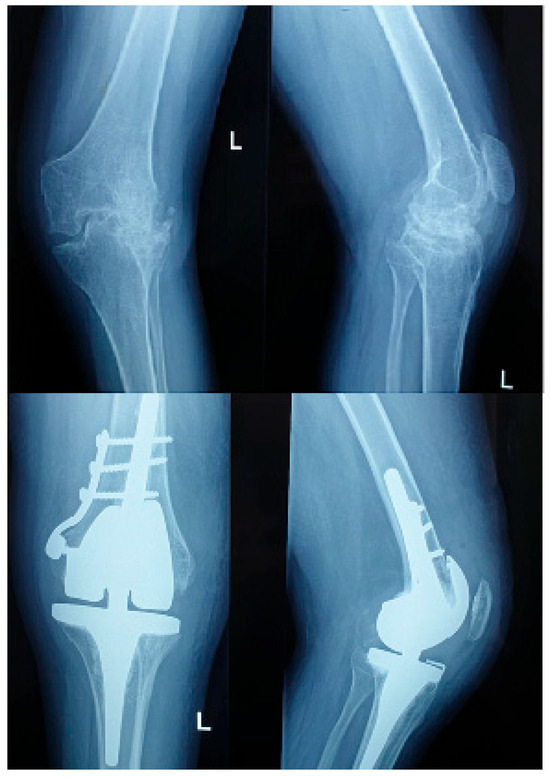

Surgical Outcomes, Complications, and Cost-Effectiveness of Total Knee Arthroplasty in Hemophilic Versus Non-Hemophilic Patients: A Comparative Study

Surgeries 2025, 6(4), 101; https://doi.org/10.3390/surgeries6040101 - 20 Nov 2025

Background: Total knee arthroplasty (TKA) is the gold standard for advanced hemophilic arthropathy. However, surgical management in hemophilic patients is complex due to joint deformities, bleeding risk, and systemic comorbidities. This study aimed to compare the surgical outcomes and cost-effectiveness of TKA in hemophilic versus non-hemophilic patients. Methods: This prospective study included 50 patients treated between 2010 and 2024 at Elias University Hospital, Romania. Group 1 included 20 male patients with severe hemophilia (2 with inhibitors); Group 2 included 30 non-hemophilic male patients. Data collection was standardized and conducted preoperatively, at 6 and 12 months postoperatively, and annually thereafter for up to 14 years following surgery. The mean follow-up duration across the cohort was 7.3 ± 3.9 years (range: 0.5–14 years), allowing for consistent long-term evaluation of clinical and functional outcomes. Study included operative time, transfusion requirements, hospitalization length, perioperative complications, functional outcomes (Knee Society Score—KSS), quality of life (EQ-5D), and cost per quality-adjusted life year (QALY). Results: Hemophilic patients had significantly longer operative times (154.5 vs. 88.7 min; p < 0.001), higher transfusion rates (45% vs. 20%, p < 0.047), and longer hospital stays (mean 12.3 vs. 6.6 days). Perioperative complications occurred in 90% of hemophilic patients (anemia requiring transfusion: 45%; compressive hematomas: 10%; wound dehiscence: 15%) compared to 10% in controls. Non-hemophilic patients achieved superior postoperative functional scores. Mean preoperative KSS was 32.25 ± 11.24 and postoperatively, the mean score increased to 98 ± 1.34. The mean preoperative KSS in the hemophilic group was 31 ± 13.93 and postoperative KSS was 74.5 ± 19.92. The cost per QALY was €2506 in the hemophilic group versus €1258 in controls. The economic assessment was conducted from the hospital perspective, focusing on direct medical costs incurred during hospitalization and the perioperative period. Cost components included factor replacement therapy, surgical and anesthesia costs, hospital stay, laboratory investigations, blood transfusions, and management of postoperative complications. Conclusion: Although TKA improves quality of life and function in hemophilic patients, it is associated with higher complication rates and costs. These findings highlight the need for careful patient selection and informed consent when considering TKA in hemophilic patients.